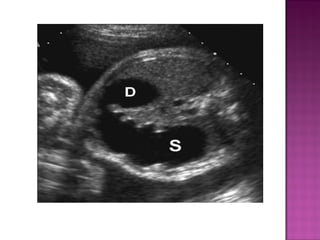

 Rare

 Usually distal

 AXR—gas filled stomach without distal

intestinal air. SINGLE BUBBLE SIGN.

 Can be dx antenatally on ultrasound.

 Rare  Usuallydistal  AXR—gas filled stomach without distal intestinal air. SINGLE BUBBLE SIGN.  Can be dx antenatally on ultrasound.